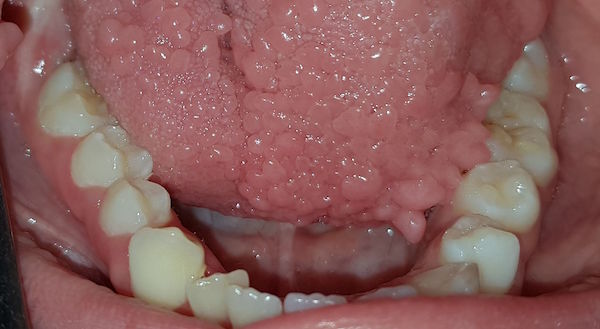

15-jähriger Patient (20.01.2016 / 4868)

Dieser Weisheitszahn gehört einem jungen Mann aus Süditalien. Er ist erst 15 Jahre und 5 Monate alt und hat bereits drei durchgebrochene Weisheitszähne - und hat sie ohne Schmerzen bekommen!

Hintergrund: Die normale Durchbruchszeit von Weisheitszähnen lag um 1970 im Kanton Zürich zwischen 18 und 22 Jahren. Offenbar kann das Wachstum auch viel rascher sein. Möglicherweise bekamen unsere Vorfahren in der Eiszeit ihre Weisheitszähne auch so früh und problemlos.